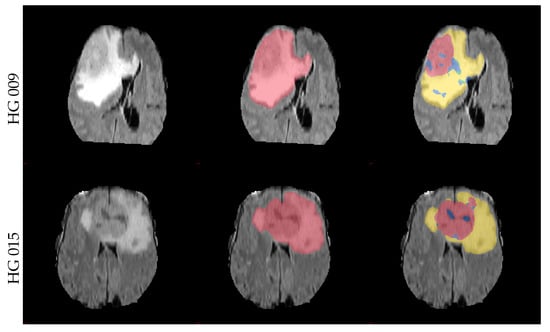

The obtained mean DICE score from leave-one-out experiments is 78.7% ± 15.7%, and the sensitivity and specificity are 78.3% ± 15.9% and 98.8% ± 1.2%, respectively. These results are inline with the expected results from other experiments and could be further improved using more sophisticated features and additional post-processing [17]. Figure 7 shows some examples of the obtained segmentation, both as two and multiclass results.

Figure 7.

Example axial and coronal (HG 006) slices from the validation set u(BraTS 2013 dataset) using the proposed PU-learning method. The colour coding is as follows: ‘yellow’: edema; ‘red’: enhancing tumour; ‘green’: non-enhancing tumour; ‘blue’: necrosis. The subject name is identical to the identifier within the original training dataset.